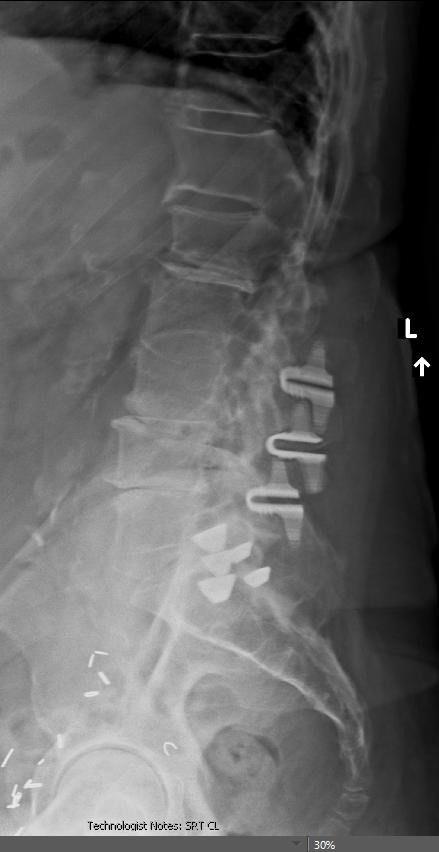

Figure. Anteroposterior (A) and lateral (B) image of a patient who had lumbar stenosis and degenerative scoliosis who was treated with L2-3, L3-4, and L4-5 laminotomies and interspinous spacers.

To treat the instability caused by lumbar decompression procedures, surgeons can fuse the unstable segments. However, there are complications associated with fusion surgery. These complications include an increased rate of infection, increased risk of nerve injury, pseudarthrosis, and a potential increased risk of adjacent segment degeneration.6-8 To counteract the potential instability caused by lumbar decompression procedures while giving surgeons an alternative to fusion, interspinous spacers were developed. Once such device is the Coflex (Figure).

The Coflex is a U-shaped titanium alloy device that is compressible but restricts motion. This device can be inserted between the spinous processes to reduce motion and permit more